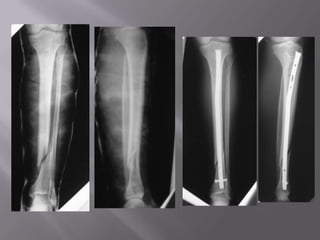

Evaluar lesión neurológica y vascular: importante examen fisicoFractura de piernaSegún la anatomía del rasgo: RxTransversales OblícuasEspiroídeasConminutas

Fractura de PiernaEstudio:Rx pierna AP, lateral.

Incluir ambas articulaciones.Tratamiento inicial:Alineamiento

Placa y tornillos.

Clavo endomedular: (goldstandar)